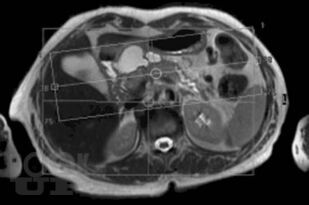

Магнитно-резонансная холангиопанкреатография

В монографии представлены современные сведения о магнитно-резонансной холангиопанкреатографии (МРХПГ). Детально отражены технические основы метода, методика и планирование исследования. Рассматриваются причины ошибок при интерпретации данных МРХПГ и способы их предотвращения и преодоления. Приведены базовые протоколы различных видов МРХПГ. Описана нормальная анатомия желчевыводящих протоков, желчного пузыря и протоков поджелудочной железы, изменения желчевыводящих протоков, желчного пузыря и протоков поджелудочной железы при патологических процессах. Отражены вопросы диагностики холангиолитиаза и оценки послеоперационной анатомии желчевыводящих протоков. Рассмотрены особенности МРХПГ при патологических изменениях комплекса большого дуоденального сосочка и двенадцатиперстной кишки. Приведены данные о МРХПГ с использованием гепатоспецифического контрастного вещества.

Каждый раздел монографии иллюстрирован.